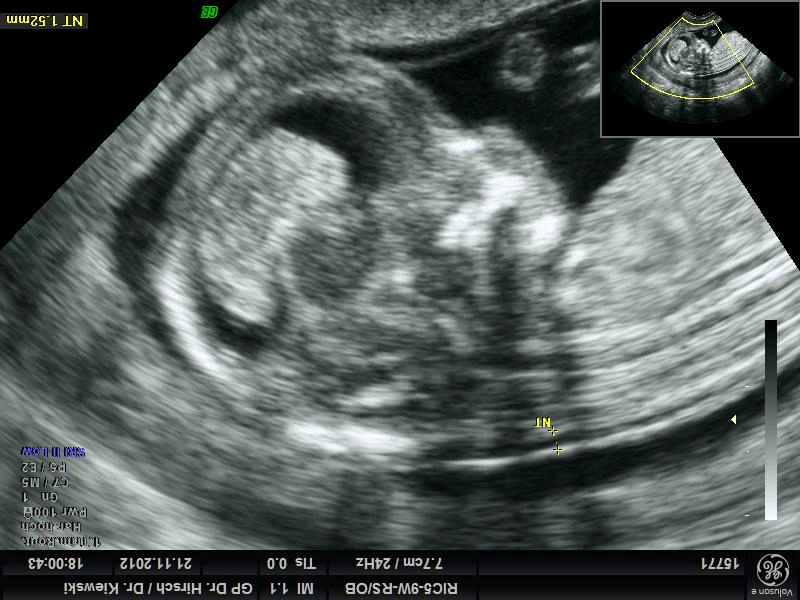

Es gibt schon in der frühen Schwangerschaft Hinweise auf derartige Störungen. Durch eine Blutentnahme bei der Mutter und durch die Messung der Nackenfalte ( Erstrimesterscreening - first-trimester-screening ) mittels Ultraschall (optimal bei 12 vollendeten Schwangerschaftswochen) kann man das Risiko für chromosomale Störungen berechnen. Auf diese Weise können bis zu 90 % der Trisomien 21 aber auch zum Beispiel andere genetische Schäden oder Infektionen erkannt werden.

Mit Hilfe eines Computerprogrammes werden aus den Ergebnissen der Blutbestimmungen von PAPP-A und free ß-HCG und dem Meßergebnis der Nackentransparenz das Risiko für bestimmte chromosomale Störungen berechnet.